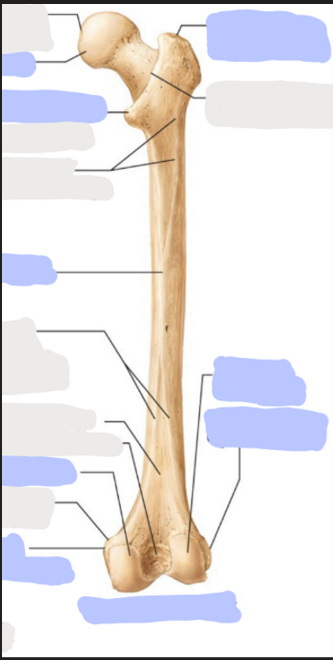

What is this picture of?

Posterior view of the Right Femur

What is here?

Where is the Head of the Femur?

What is here?

Where is the Lesser Trochanter of the Femur?

What is here?

Where is the Linea Aspera of the Femur?

What is here?

Where is the Medial Condyle of the Femur?

What is here?

Where is the Medial Epicondyle of the Femur?

What is here?

Where is the Greater Trochanter of the Femur?

What is here?

Where is the Lateral Condyle of the Femur?

What is here?

Where is the Lateral Epicondyle of the Femur?